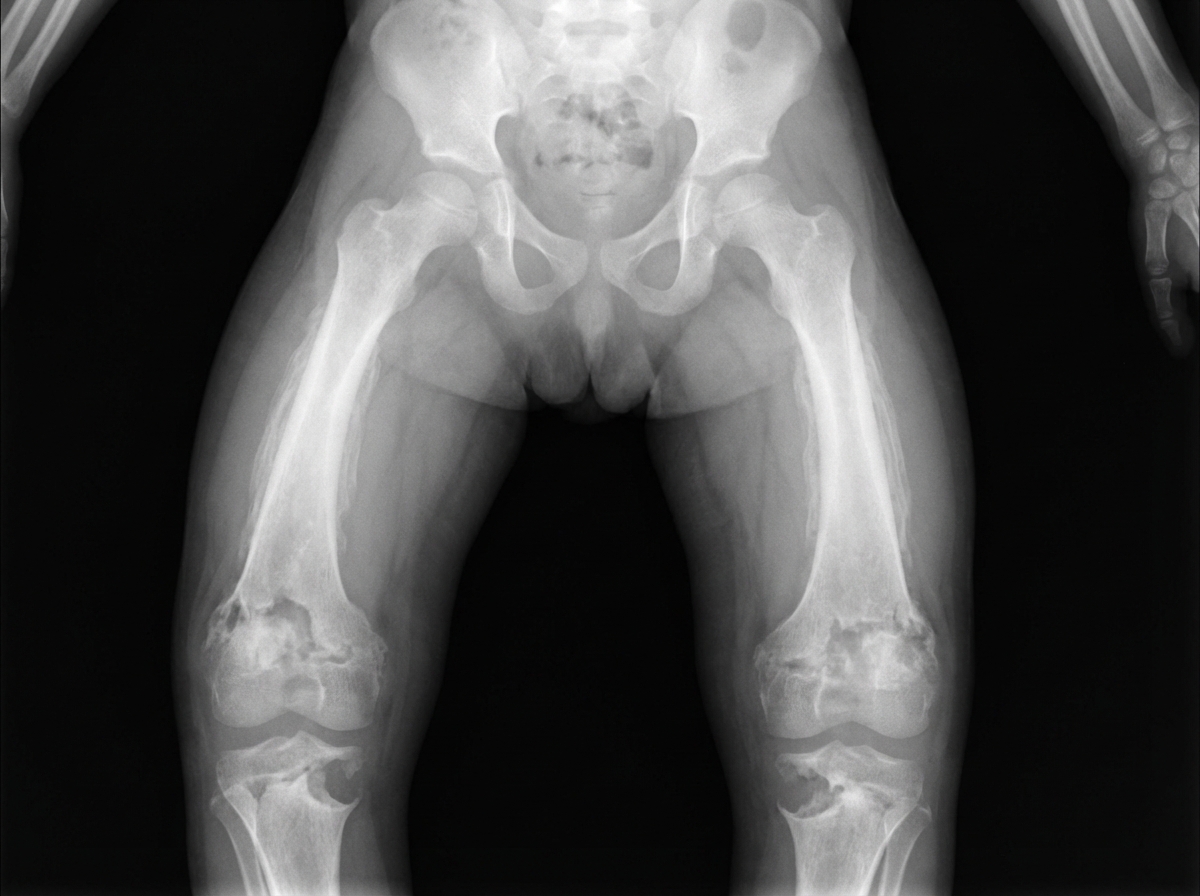

A fetogram of a stillborn infant is shown below. What is the most likely diagnosis?

Explanation: ***Congenital syphilis*** - Characteristic **skeletal abnormalities** on fetogram include **periostitis**, **osteochondritis**, and **metaphyseal irregularities** affecting long bones. - **Wimberger sign** (bilateral destruction of the proximal medial tibial metaphysis) is pathognomonic for congenital syphilis on radiographic imaging. *Congenital varicella syndrome* - Primarily causes **limb defects**, **cortical atrophy**, and **cicatricial skin lesions** rather than distinctive bone changes. - Skeletal manifestations are typically **limb hypoplasia** and **shortened extremities**, not the periostitis seen in syphilis. *Congenital lupus* - Mainly presents with **cardiac conduction defects** (complete heart block) and **cutaneous manifestations** (neonatal lupus rash). - Does not typically cause the characteristic **bone lesions** or **periostitis** visible on fetogram imaging. *Congenital CMV infection* - Radiographic findings include **intracranial calcifications**, **microcephaly**, and **growth restriction** rather than bone abnormalities. - Skeletal involvement is rare and does not produce the **metaphyseal changes** and **periostitis** characteristic of syphilis.